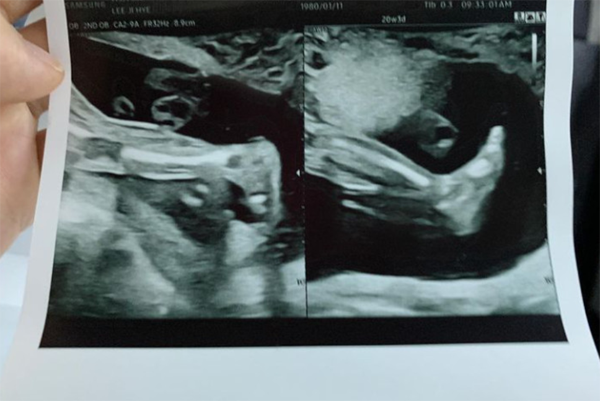

이지혜와 문재완 부부는 둘째 임신을 위하여 난임 센터를 방문해 시험관 시술을 하며 많은 노력을 해왔는데요. 세 번째 시험관 시술을 통해 임신에 성공 현재 8월 기준으로 임신 6개월에 접어들었다고 하며 최근 초음파 사진을 공개하기도 했습니다.

이어 이지혜는 인스타그램에 둘째 아이의 초음파 사진을 공개하며 "태교는 1도 못하는데 알아서 잘 크고 있는 우리 둘째. 미안하고 고마워. 건강하게 있다가 만나자"라고 애정 가득한 글을 남겼습니다.